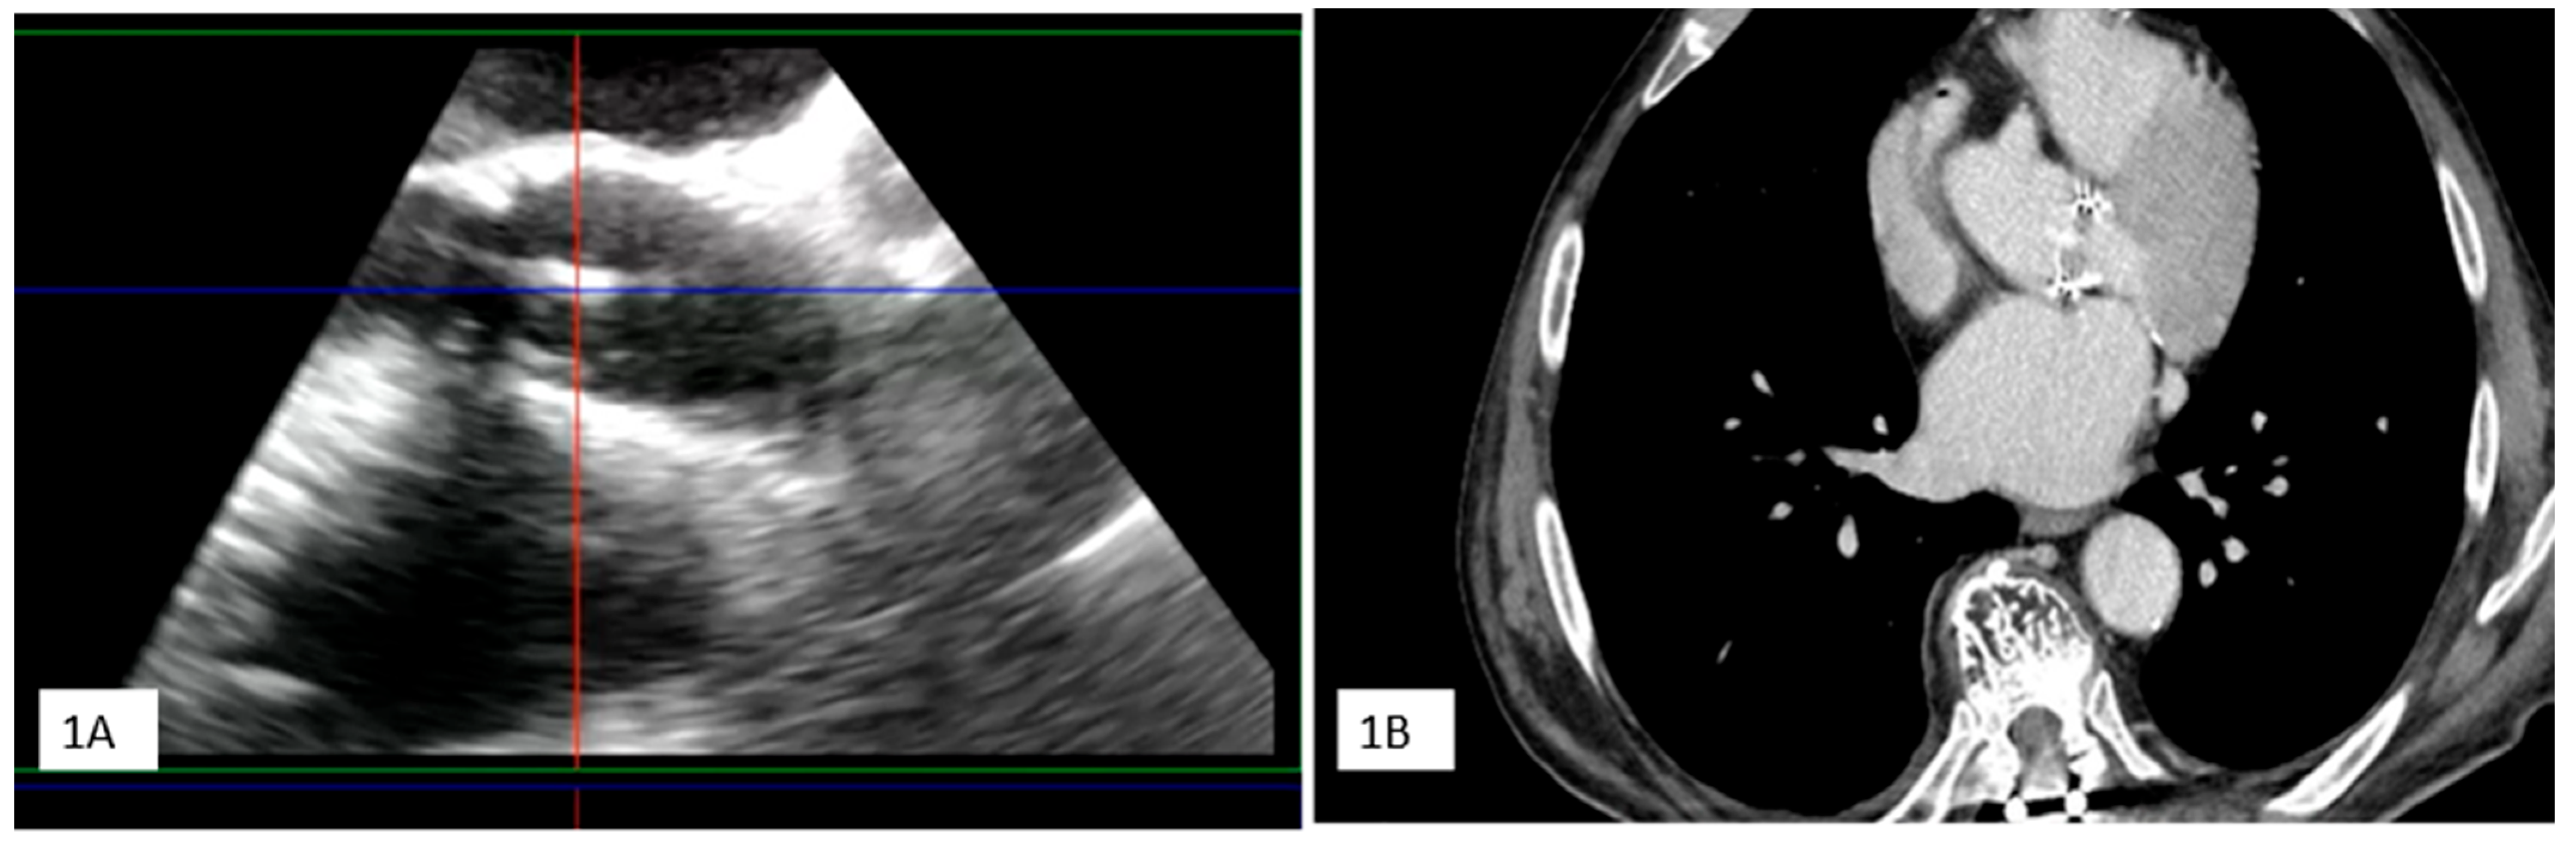

Clinical Case 1. A 38-year-old woman without pre-existing cardiac disease was admitted for 10-day mild fever associated with progressive epigastric pain and vomit one month following piercing implant. Clinical examination revealed a painful hepato-splenomegaly. Cardiovascular evaluation showed tachycardia (120 beat/min), arterial hypotension (75/45 mm Hg) without any cardiac murmur. Abdomen echo scan confirmed a normally structured hepatosplenomegaly, together with inferior vena cava enlargement suggesting venous congestion. Blood chemistry showed increased white cell count (12,860) and severe anemia (Hb3.9), requiring urgent transfusion. C-reactive protein was moderately high (16.5). Blood culture was positive for methicillin sensitive S. aureus. TT (1) and subsequent TEE (2,3,4) showed a large iso-echogenic vegetation (yellow arrow), which was attached to the atrial surface of the anterior leaflet of the tricuspid valve, prolapsing into the right atrium during the systole and determining related severe valve regurgitation. The patient underwent culture-guided antibiotic therapy with disappearance of the vegetation and reduction in tricuspid regurgitation to a moderate degree at subsequent echocardiographic examination.

![]() |